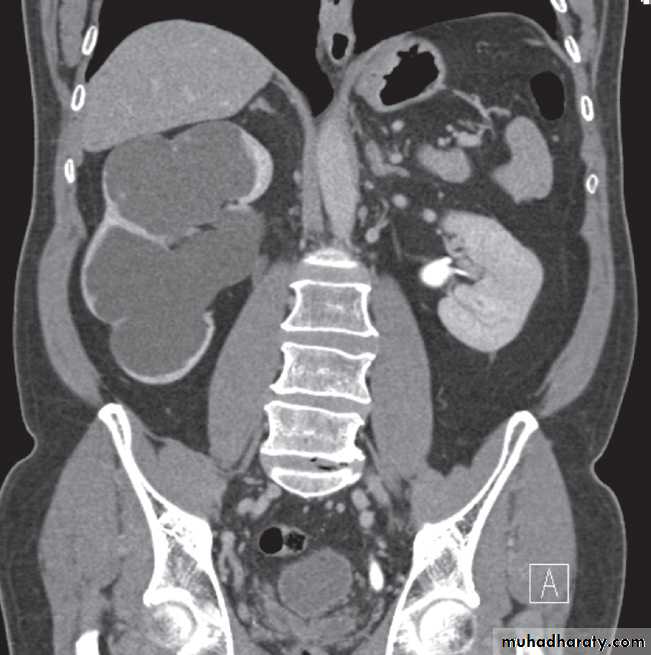

Ultrasound Dilatation of the pelvicaliceal system ( hydronephrosis ) is demonstrated sonographically as a multiloculate fluid collection in the central echo complex, caused by pooling of urine within the distended pelvis and calices .

Major DDX are multiple renal cysts. With prolonged obstruction, thinning of the cortex due to atrophy will be seen.

Solitary masses arising within the renal parenchyma are either malignant tumours or simple cysts .In adults, amalignant tumour is almost certain to be a renal cell carcinoma, whereas in young children it is usually Wilms’tumour.

Renal masses are usually first detected at ultrasound examination.Ultrasound can establish whether a mass is a simple cyst and can, therefore, be ignored, or whether the lesion is solid and, therefore, is likely to be a renal carcinoma.( further evaluation with CT is indicated ) .

The initial diagnosis of a renal mass is now rarely madeon IVU as ultrasound and CT are the usual primary modalities.Computed tomography

-A typical simple renal cyst is a spherical mass with an imperceptible wall . The interior of the cyst is homogeneous with attenuation values similar to water.

-Renal cell carcinomas are approximately spherical and often lobulated .With density similar to renal parenchyma or slightly less with often seen some areas of necrosis & calcification .

Wilms’ tumour is the likely diagnosis in a child with a renal mass. These lesions are frequently large and may contain stippled calcification